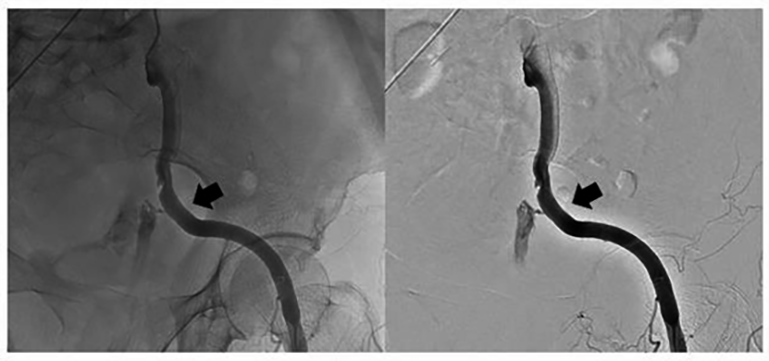

Fig. 5.The second covered stent was placed and partial overlap the front one (arrow).

Emergency vascular interventional surgery was promptly performed while haemostasis and treatment of shock was administered simultaneously. The covered stent was placed rapidly in the ruptured external iliac artery pseudoaneursm to block the bleeding source and it also ensured blood supply to the lower limbs. However, it should be noted that she needed to undergo a second interventional surgery 5 hours later. This could have been related to leakage of the covered stent or increased blood pressure and vasodilation. Moreover, clinicians should be alert to complications such as stent obstruction, deformation and kinking, stent loss, intimal hyperplasia and infection after placement [24]. However, no such complications were observed in the patient during follow-up.